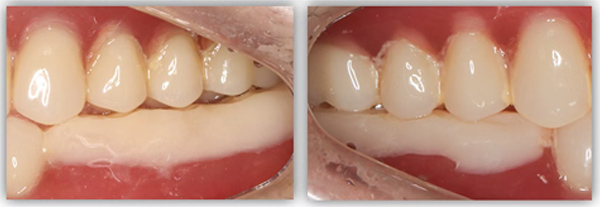

單顆是最常規(guī)的種植,不能因為常規(guī)就覺得簡單,治療時要追求小而精。從適應(yīng)證把握到術(shù)式選擇,再到修復(fù)方式,術(shù)后的結(jié)果有沒有達(dá)到術(shù)前預(yù)期效果,都需要用心設(shè)計,事后復(fù)盤。這位患者是一位來自外地的年輕老師,有一顆6號牙需要種植。她只有在暑假兩個月的時間內(nèi)可以來院,希望能在暑假期間完成治療。

為滿足患者的需求,我為她制訂了一個即拔即種、種植后早期負(fù)重的方案,把五個治療步驟縮減為三步。首次來院時,我為她完成了拔牙、種牙和安裝基臺,6周后來院拆線和取模,兩周后完成牙冠修復(fù),也就是戴牙。整個治療周期僅8周,不到兩個月就完成了。

6號牙也就是第一磨牙,是最早萌出的恒牙,比較容易齲壞。它雖然不在前牙美學(xué)區(qū),不太容易影響容貌,但出于對美學(xué)的高要求,我在設(shè)計方案時也考慮了是按常規(guī)流程先拔牙,再備洞,還是以修復(fù)為導(dǎo)向,先按現(xiàn)有的牙冠來確定未來修復(fù)體的形狀,再去反推種植體植入的位置。后者對醫(yī)生來說難度更高一些,但更有利于復(fù)原天然牙的形態(tài)。

為保證這個方案的順利實施,我通過查閱文獻(xiàn)去印證方案的可行性,還為她建議了適合的種植體,原來三個月的骨結(jié)合時間能縮短為兩個月,種植體功不可沒。